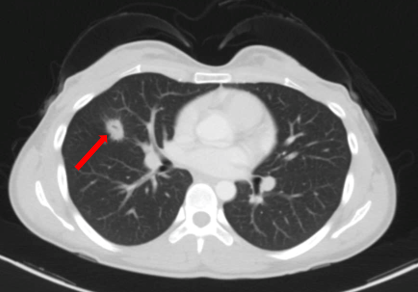

Sau đó bệnh nhân được chỉ định thêm các xét nghiệm cận lâm sàng khác. Trên phim chụp cắt lớp vi tính lồng ngực của bệnh nhân phát hiện khối u phổi dạng nang kích thước ~ 20x14mm ở thùy giữa phổi phải.

Hình 2. Hình ảnh khối u phổi phải trên phim chụp Cắt lớp vi tính ngày 27 tháng 10 năm 2022 (mũi tên).